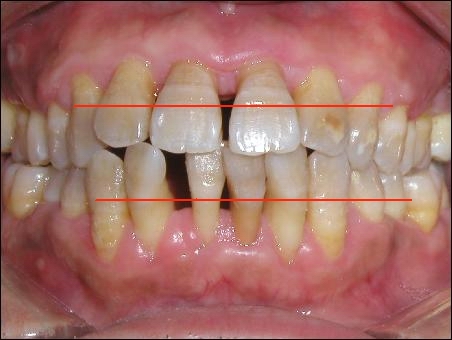

患有牙周病的牙

正常的牙齦應(yīng)該在紅線的位置,但現(xiàn)在已因牙周病而萎縮。牙齒顯得很長,那些黃色的印記,是原來牙齦所在的位置,而現(xiàn)在,它就像河水干涸之后,裸露的巖石,標(biāo)志著一個人歷經(jīng)的歲月滄桑。牙醫(yī)們經(jīng)常會告訴你一句話,被吸收的牙槽骨是不可能再生長的。換言之,一旦牙槽骨被吸收了,這個過程是不可逆的。但事實上,人的骨骼就像人的肉一樣,在一定程度上是可以再生的。當(dāng)然我的意思并不是說,把腿砍了,可以再長出一條腿,而是說,如果你骨折了,斷了的地方是會接上的。而且接上的地方甚至比沒有斷過的地方長的還結(jié)實。其實長上的并非是骨頭,而是被一些類骨組織,像膠原蛋白形成的組織包裹住了,就像樹上長的結(jié)子一樣。因此,凡是得了牙周病的人,基本可以肯定地說,他體內(nèi)的蛋白質(zhì)開始慢慢變少。而蛋白質(zhì),是組成生命活動最基本的組織---細胞中,除水以外的最主要物質(zhì)。人體的衰落,從牙齒上可以略見一斑。